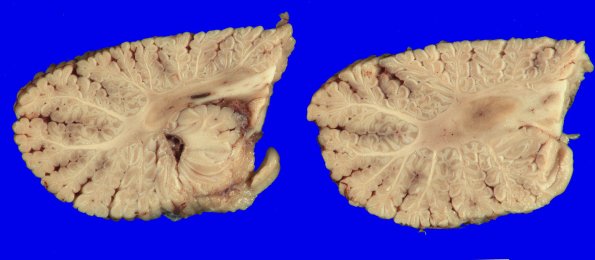

16A9-10 The fixed neocerebellum shows little atrophy and significant white matter discoloration.